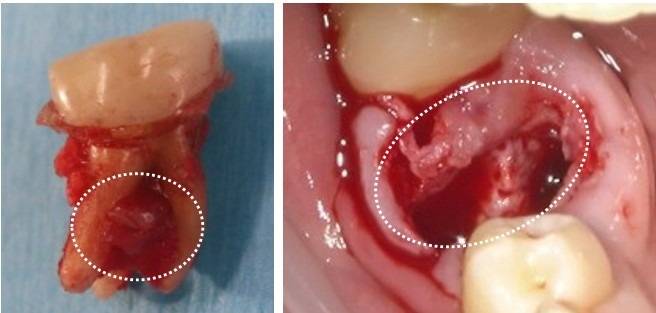

骨造成術(手術)の実際

資料